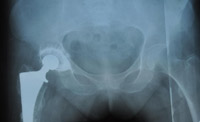

С  2009г  начали  выполнять  протезирование  тазобедренного  сустава  однополюсными  гемипротезами.  Широко  используется  накостный  остеосинтез,  интрамедулярный  остеосинтез  с  блокированием,  чрезкостный остеосинтез  (ЧКОС).

"до операции"